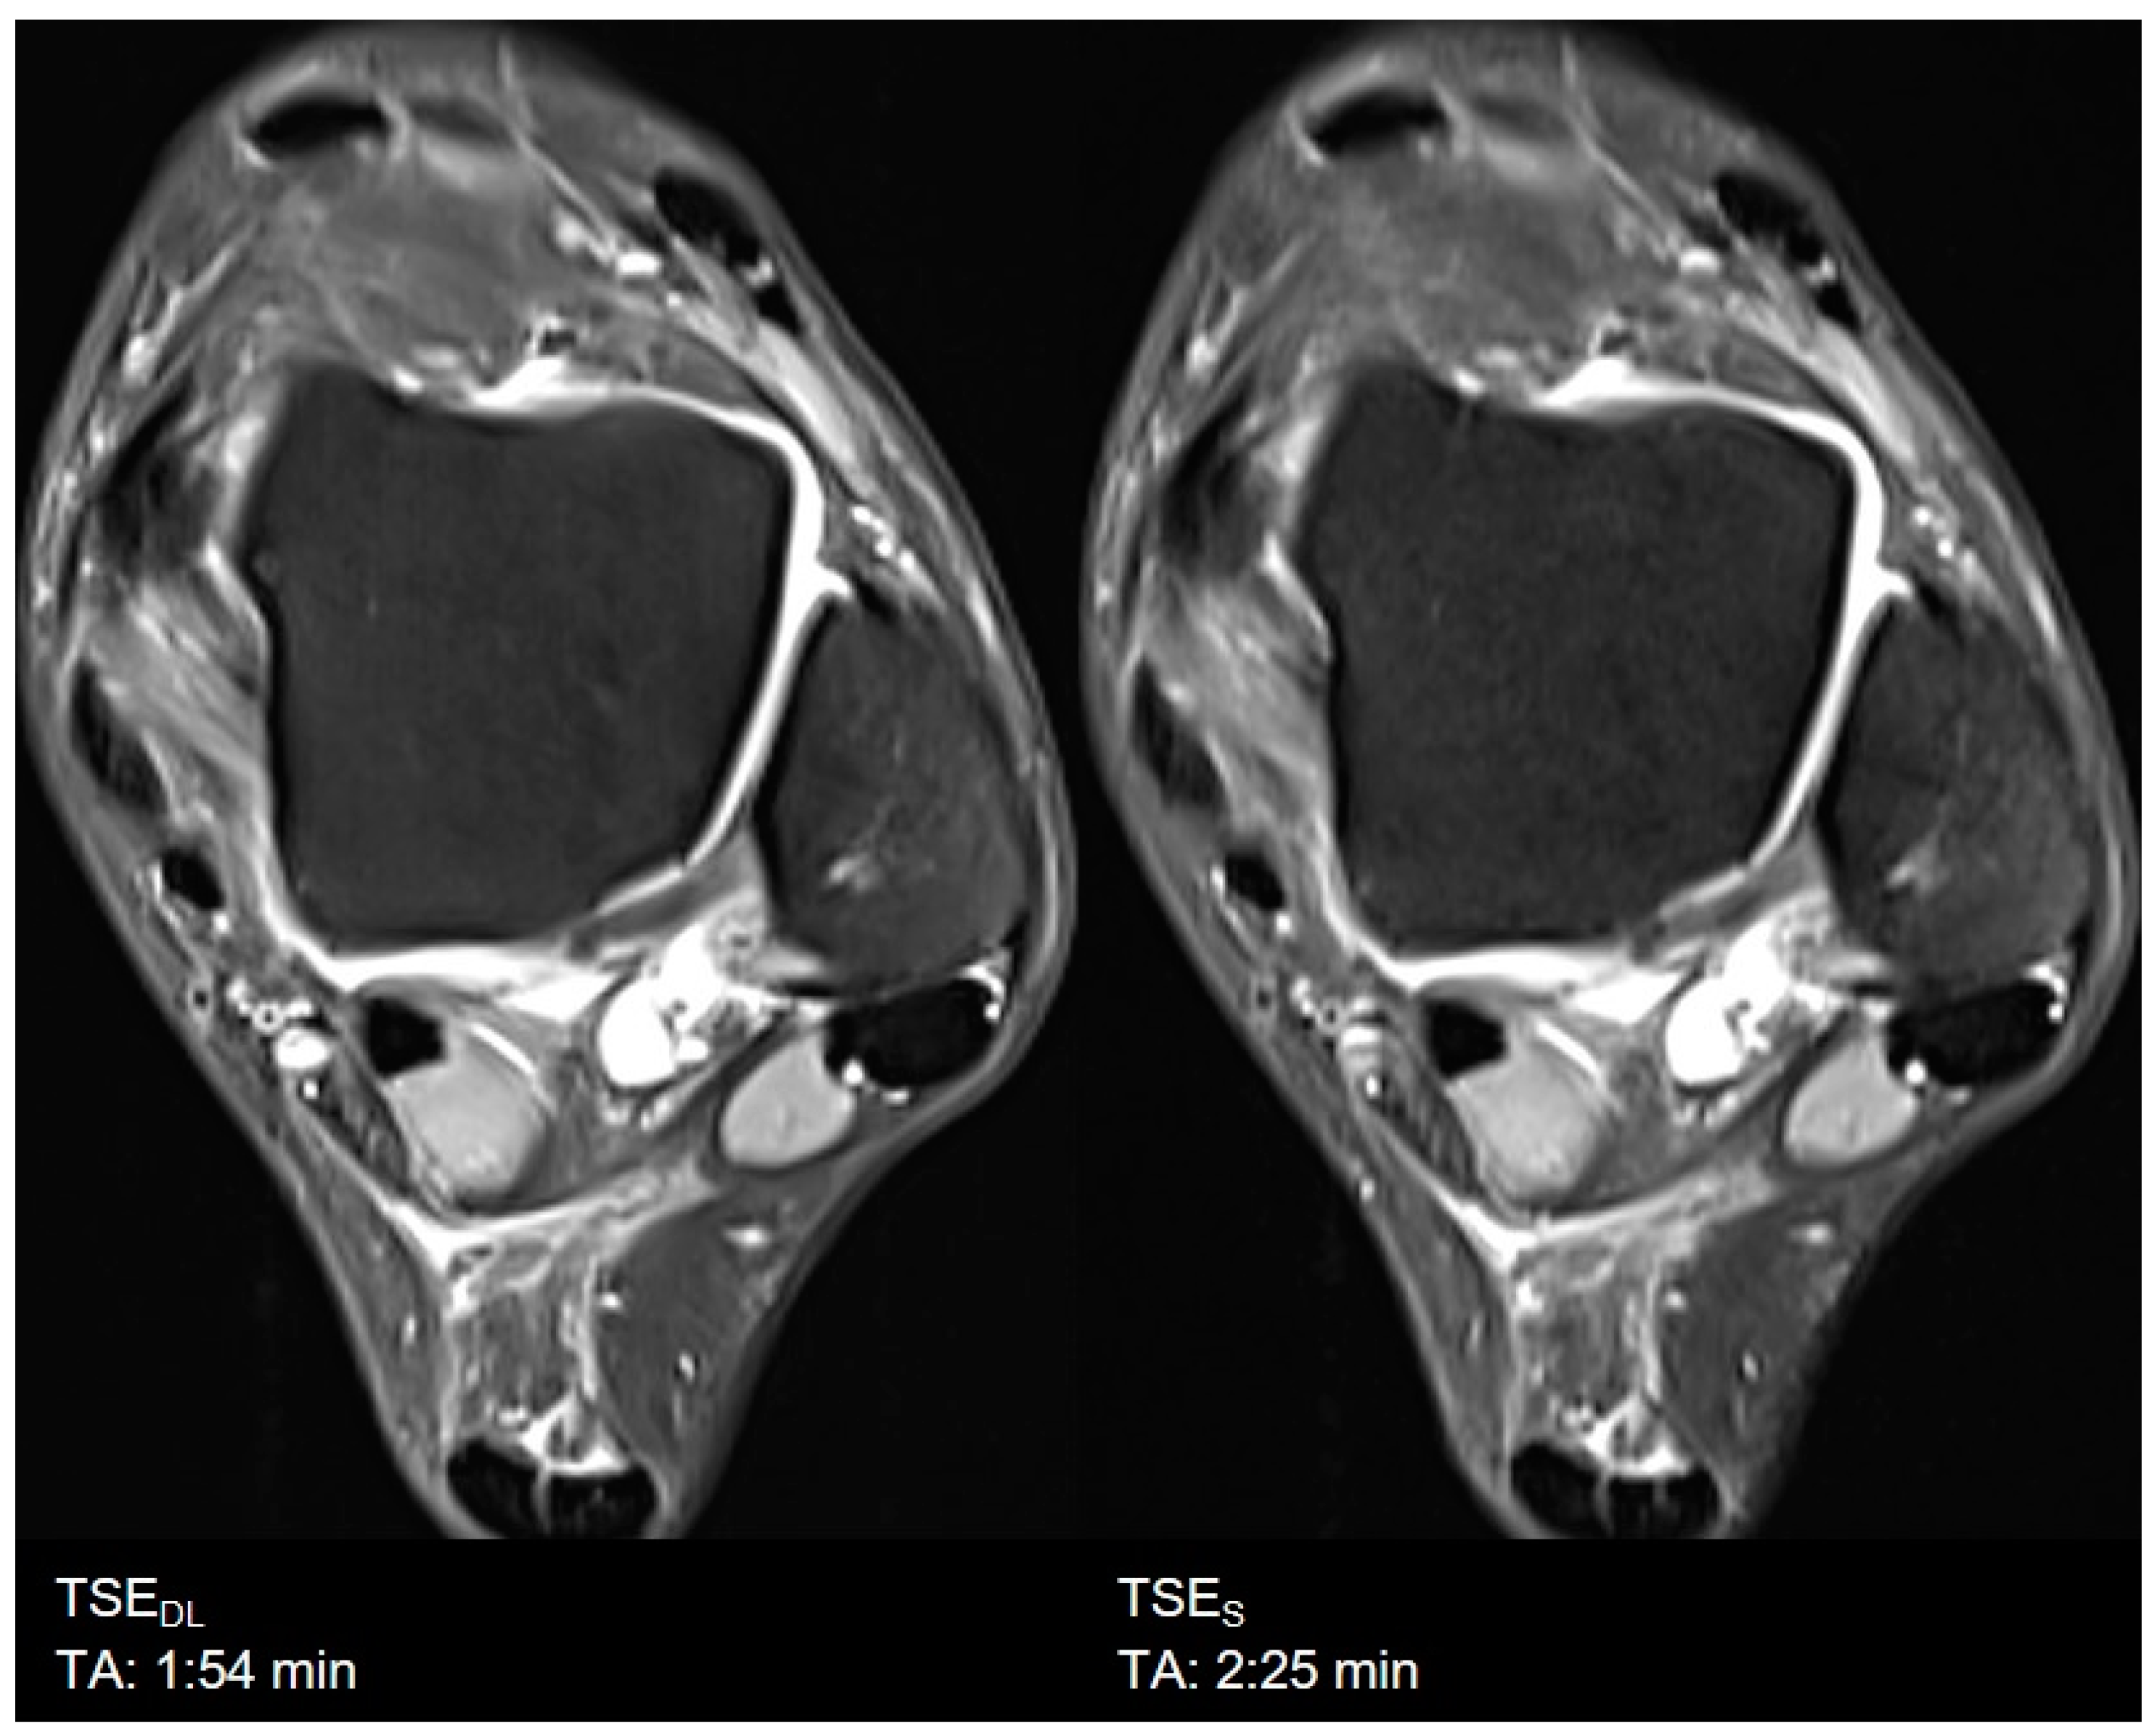

3. Results

3.1. Assessment of Image Quality

3.2. Assessment of Anatomical Structures